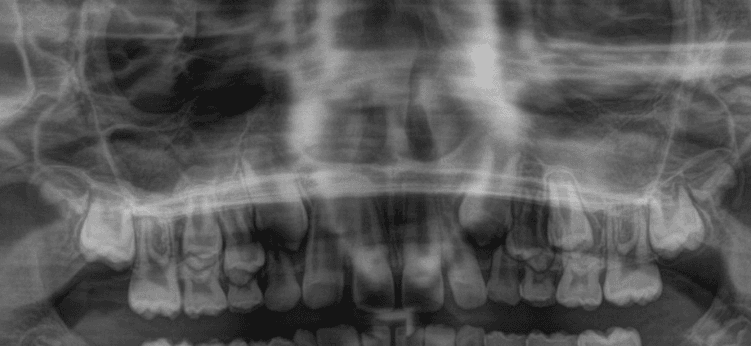

Achados radiográficos radilúcidos:

Achados radiolúcidos em radiografias podem ser indicativos de várias condições que afetam a saúde bucal e precisam ser considerados e avaliados antes de realizar movimentações ortodônticas. Alguns achados mais comuns são:

Cáries: Devem ser tratadas antes do início do tratamento ortodôntico, para evitar complicações, uma vez que a progressão da cárie pode afetar a estrutura dentária e saúde periodontal.

Lesões periapicais: Devem ser tratadas adequadamente com endodontia antes do início da ortodontia e acompanhamento radiográfico.

Cistos: A presença de cistos pode interferir os movimento ortodônticos e a saúde bucal em geral. O tratamento ortodôntico pode ser contraindicado até que a condição seja resolvida, geralmente com cirurgia ou outros tratamentos médicos.